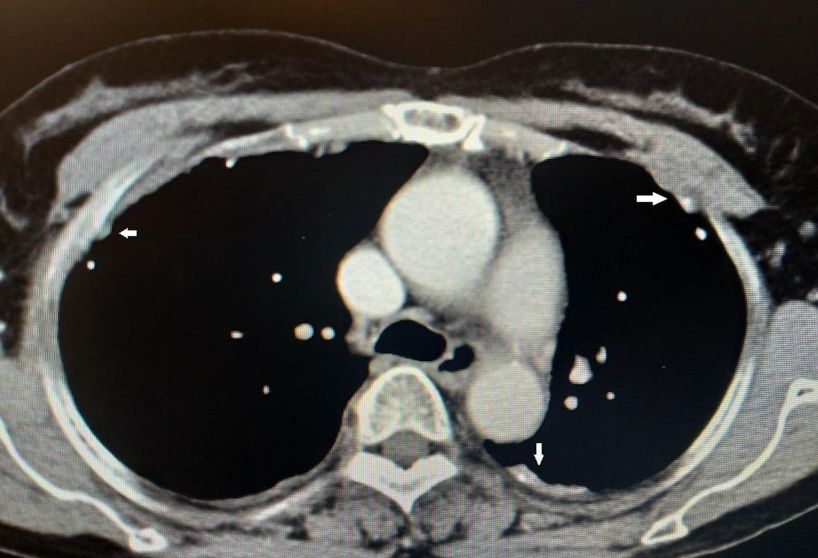

•入院后查血肿瘤标志物正常,T-SPOT阴性。胸部CT见两肺内少许絮索条影,两侧胸膜结节状增厚伴散在钙化。

图示:患者两侧胸膜可见结节、钙化影(白箭)

到目前为止,除了胸腔积液之外,仔细阅读该患者胸部CT发现该患者的另外一个特点就是胸膜增厚、结节、钙化影。通过这一线索,不排除有胸膜来源疾病的可能。